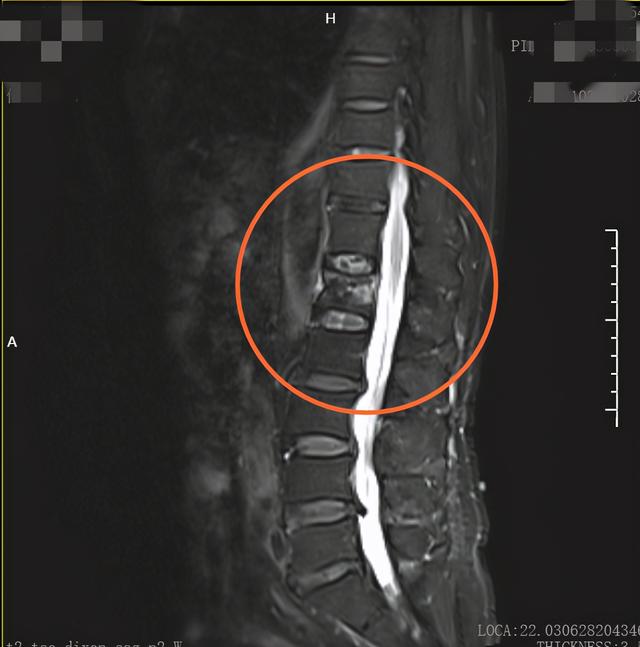

▲术前检查显示L1椎体骨折变扁。

患者入院后完善相关检查,并多次练习确认俯卧位可以坚持1小时,在第三天早上,骨科金勋杰主任团队做好术前准备,由金勋杰主任主刀,行球囊扩张椎体后凸成形微创手术。手术在局麻下顺利完成,经过医护人员的精心照顾,术后患者恢复良好。

▲术后,L1椎体压缩性骨折骨水泥填充术后,L1椎体内见团片状密度增高。